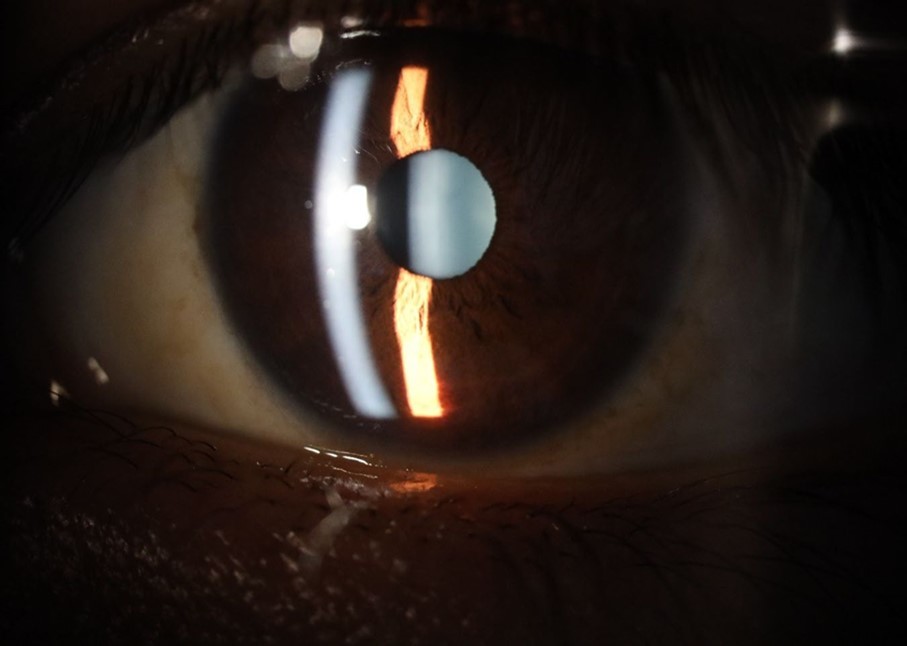

Figure 25.Mirror reflection of the affected eye (right side), with good appearance. This indicates that the transparent media of the eyeball (Cornea, anterior chamber, lens, and vitreous) are in good condition.

Figure 26.The macrograph of the anterior segment of the right eye (affected) shows very good transparency of the cornea, anterior chamber, lens, and vitreous.